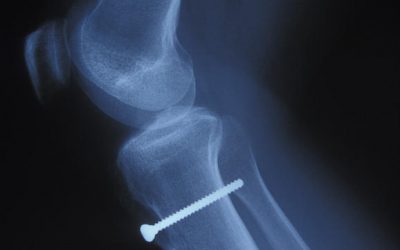

Se olvidaron retirar un tornillo. Moya & Marín ha vuelto a obtener una sentencia condenando al Servicio Andaluz de Salud, por una negligencia médica cometida a un cliente nuestro. En concreto, a...